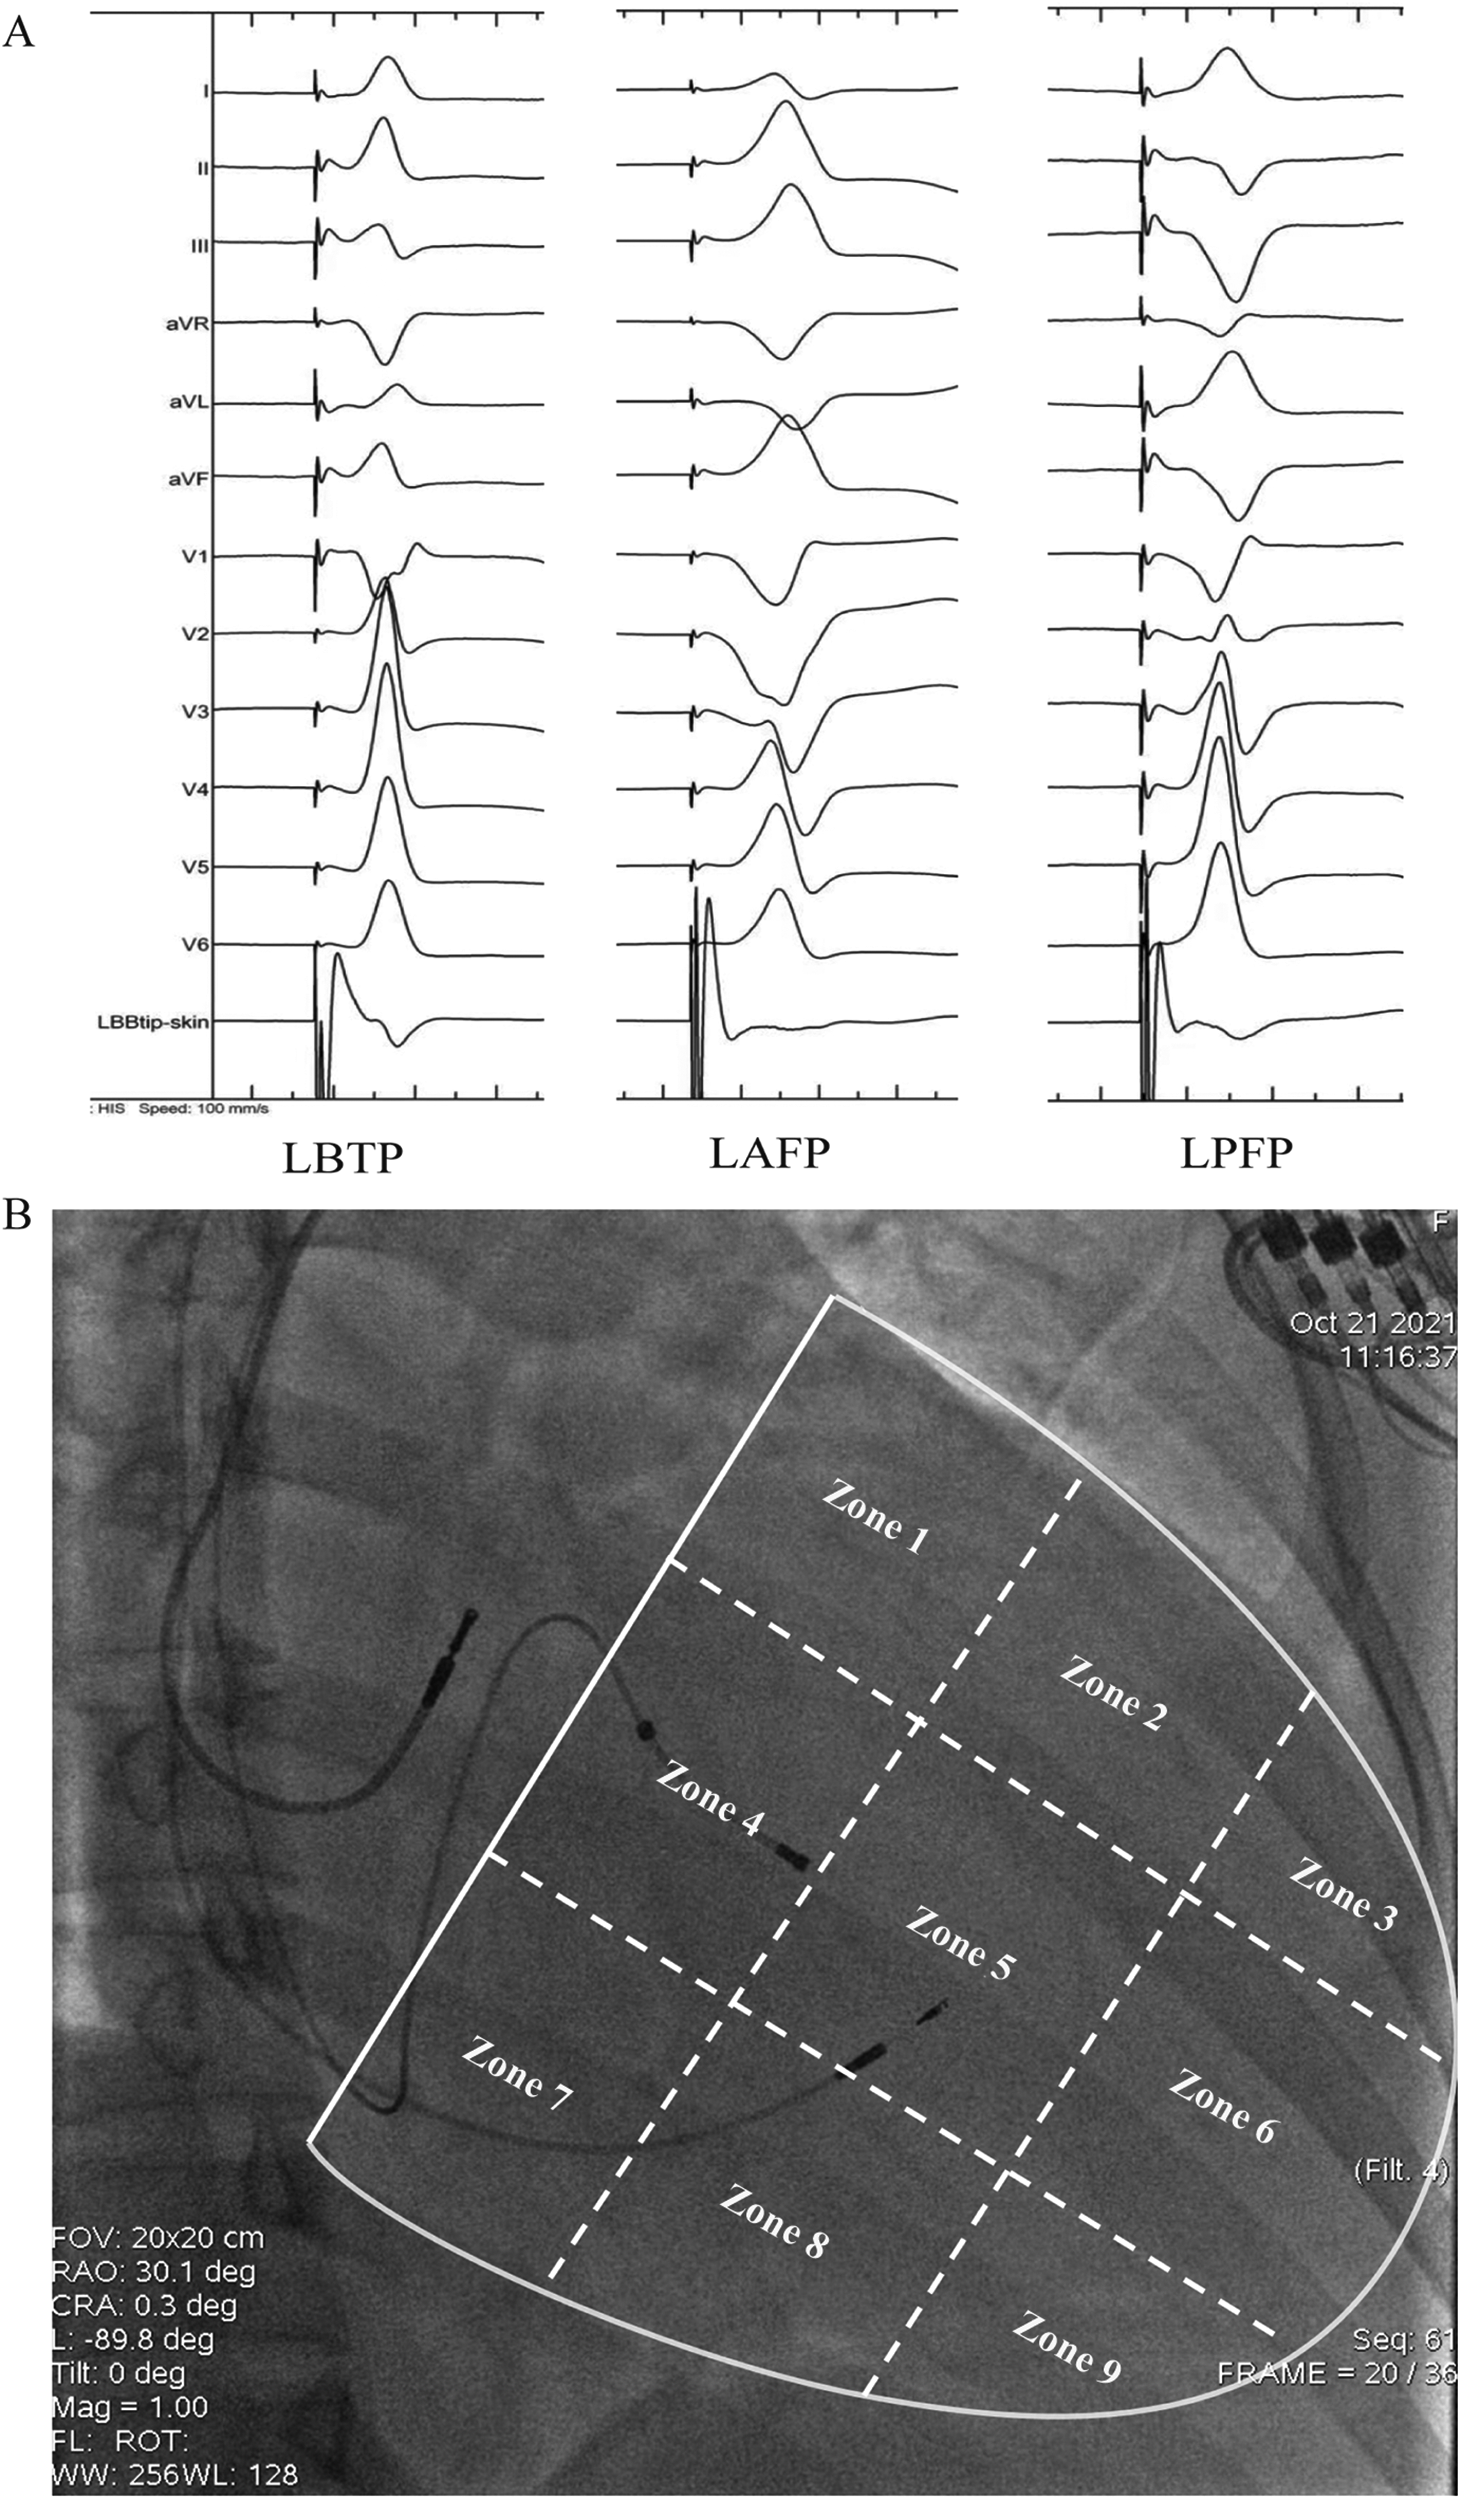

The QRS morphology of LBBAP under VVI mode and unipolar pacing was analyzed to determine the paced branch of left bundle (LBTP, LAFP or LPFP). The paced ECG criteria were as follows (2, 15, 16): (1) LBTP: frontal QRS axis close to normal; dominantly positive QRS waves in lead II; negative component present in lead III; (2) LAFP: right-axis deviation; dominantly positive QRS waves in lead II and lead III; dominantly negative waves in leads I and aVL; (3) LPFP: left-axis deviation; dominantly negative QRS waves in lead II and lead III; dominantly positive waves in leads I and aVL (Figure 1A).

Figure 1

Schematic diagram of grouping based on paced QRS morphology (A) and distribution of lead tip using the 9-partition method (B). LAFP, left anterior fascicle pacing; LBTP, left bundle trunk pacing; LPFP, left posterior fascicle pacing.

2.4 Fluoroscopic location of the LBBAP lead tip with the 9-partition method

As previously described, ventricle boundary between atrioventricular groove and apex was divided into 9 partitions under RAO 30° fluoroscopy (22). Briefly, a line through coronary sinus ostium (a transparent area under fluoroscopy) and meanwhile parallel to atrioventricular junction was identified as the atrioventricular groove, which was then divided into three identical parts by two vertical lines along the long-axis of ventricle. The long-axis lines were then divided into three identical parts by two short-axis lines parallel to atrioventricular groove. With these four lines, the area between atrioventricular groove and ventricular apex was divided into 3 × 3 partitions. The partition diagram is shown in Figure 1B.